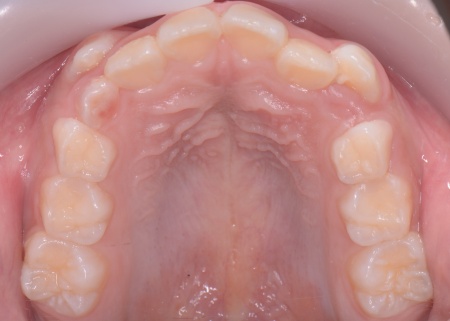

まず、上顎に顎の骨を広げるための固定式の矯正器具「急速拡大装置」を、下顎には歯並びの幅を広げるための「リンガルアーチ」を装着します。

治療を進めた結果、上顎は約6mm拡大し、歯が並ぶためのスペースを確保することができました。

次に歯の位置を整えるため、ワイヤー矯正を開始します。

上前歯6本と左右の奥歯の表面に「ブラケット」と呼ばれるボタン状の装置を設置し、そこにワイヤーを通して歯を少しずつ動かしていきました。

この装置は、歯の高さや位置のばらつきを整える「レベリング」を行うためのもので、拡大によって確保したスペースを活かしながら、歯並びを段階的に整えます。